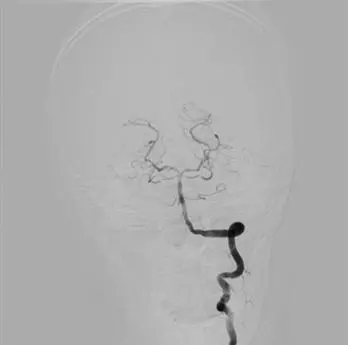

經(jīng)過四十分鐘的取栓后,終于可見血流清晰通過,至此,生命的通道被重新開通,患者在手術(shù)臺(tái)上已逐漸恢復(fù)清醒。

術(shù)后